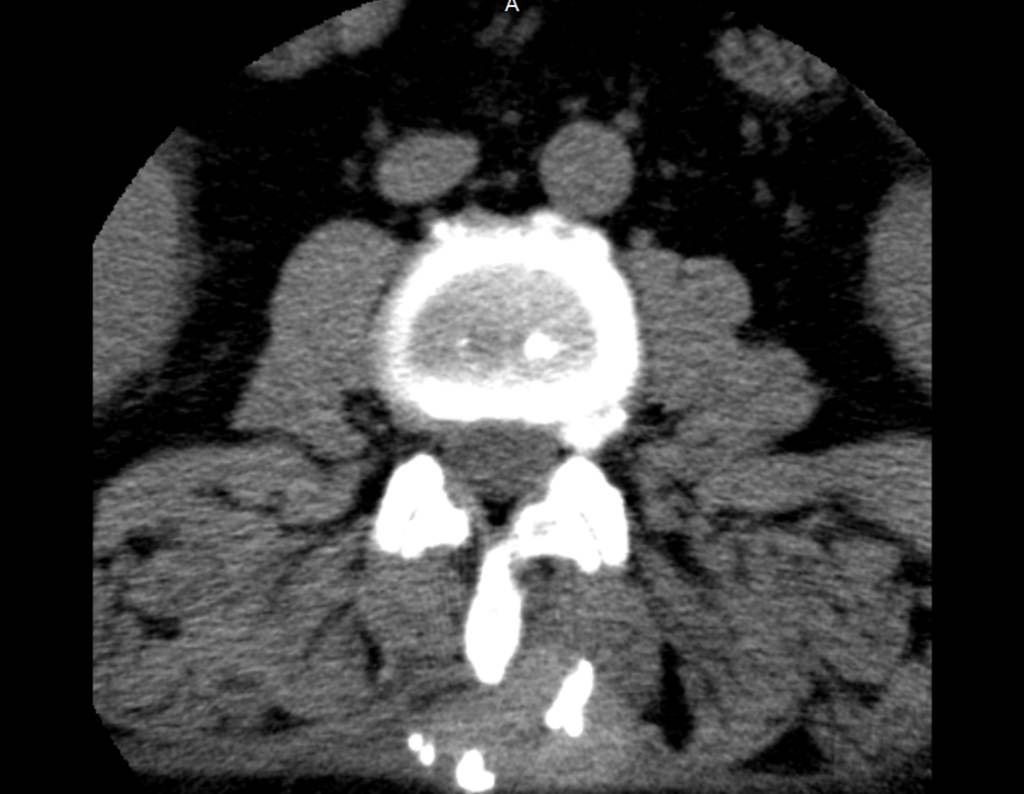

Tomografia Computadorizada (TC): A tomografia evidenciou o limite proximal da lesão infiltrando a musculatura paravertebral esquerda, com calcificação próxima à face externa da lâmina. Cortes axiais mostraram a lesão presa à asa do ilíaco esquerdo, com inúmeras calcificações e protrusão em direção à pele. A lesão acometia a parede externa do hemisacro e da pelve esquerda, com superfícies anfractuosas.

Ressonância Magnética (RM): A RM sagital T1 e T2 revelou uma lesão heterogênea na região anterior e posterior do sacro, com focos de calcificação, superfície irregular e espessa capa cartilaginosa, acometendo parte de S3. Cortes axiais T2 mostraram a lesão na musculatura paravertebral e na região posterior do ilíaco esquerdo, com sinal alto periférico e baixo no centro.